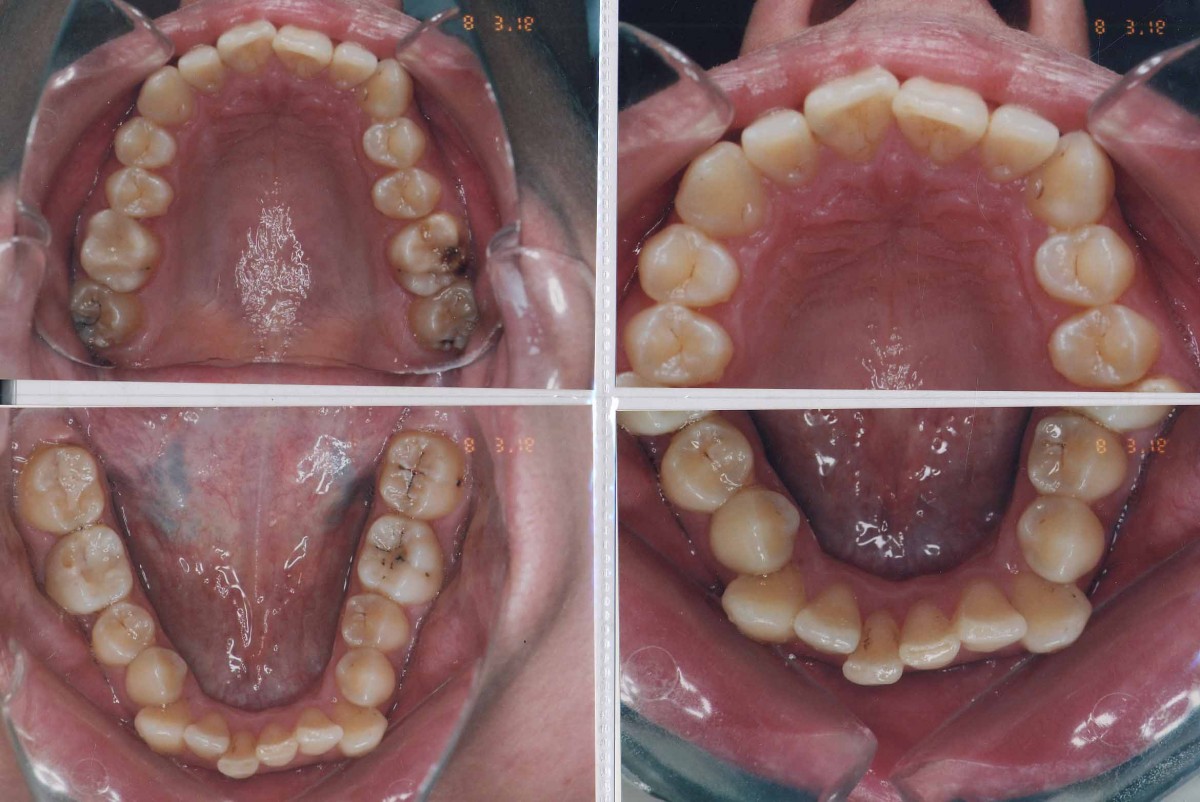

Pacient 23 ani. Extracție 1.4, 2.4, 3.5, 4.5, aparat ortodontic fix ceramic.